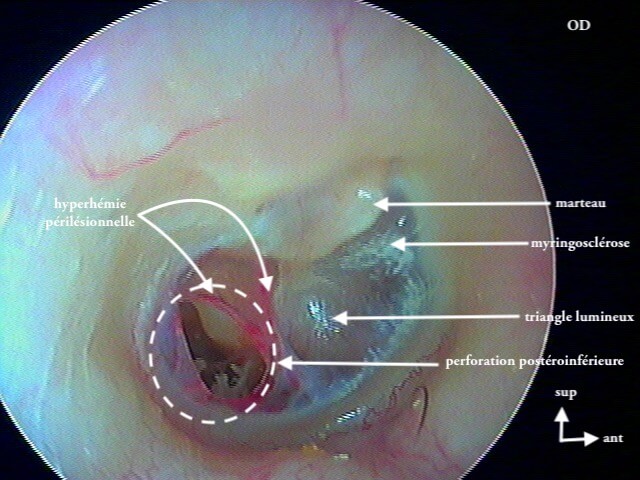

3/4 post otitique récente

Ici une otite séromuqueuse gauche perforée cicatrisée à 1 mois (cicatrice inférieure)

Une otite séromuqueuse droite perforée (et non otite moyenne aiguë)

7 MYRINGOSCLÉROSE (ou TYMPANOSCLÉROSE)

Surcharge calcaire de la couche conjonctive tympanique: AUCUNE conséquence anatomique ou fonctionnelle (auditive), gêne parfois en cas de tympanoplastie. On parle plus de tympanosclérose quand ces plaques de calcaires (issues d'infections antérieures cicatrisées) sont dans la caisse; et de myringosclérose quand elles ne touchent que le tympan. En les voyant cela vous permettra d'affirmer que le patient·e a eu des otites dans l'enfance et puis c'est tout! Ces plaques sont superficielles et le tympan est normal, à ne pas confondre avec un cholestéatome.